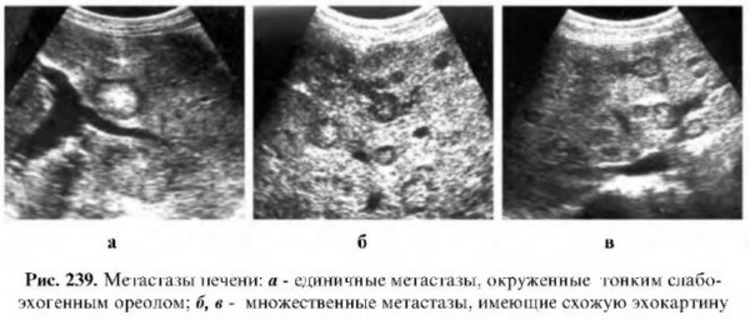

- Солитарные (один очаг).

- Единичные (2-3 точки опухолевого роста).

- Множественные.

- УЗИ, или ультразвуковое исследование.